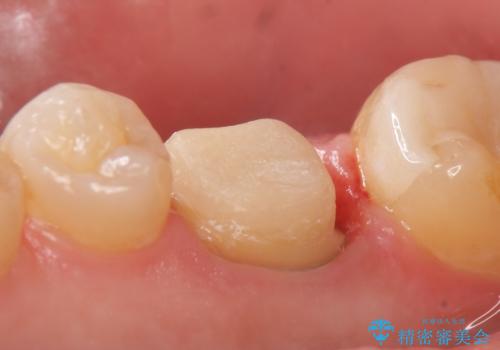

検査の結果X線上で右下6に根尖病変を認めたため、再根管治療を行いました。

症状が治まったのを確認後、オールセラミッククラウンによる補綴を行いました。

今回用いたオールセラミッククラウンはジルコニアフレームという白い素材の上にセラミックを盛っているため、審美性が非常に高いのが特徴です。